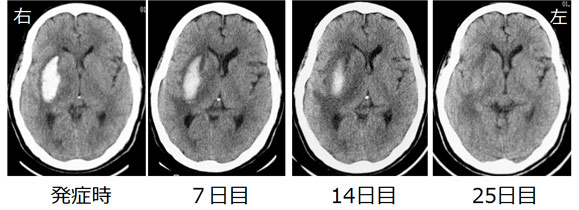

76歳 男性 診断:高血圧性脳出血(被殻出血)

上のCTは同じ患者さんの、同じ部位のCTを時間を追って見ています。白く映る部分が出血です。

7日目には出血の辺縁がボンヤリしてきて、全体的に色が薄くなってきています。14日目には更に辺縁がボンヤリとなり、出血が吸収されてきているのがわかります。25日目には、その写真だけ見ても出血の存在がはっきりしないようになっています。脳の中でも、手足を打撲して皮下出血した時と同じように時間が経過すれば、出血は徐々に吸収されていくものです。